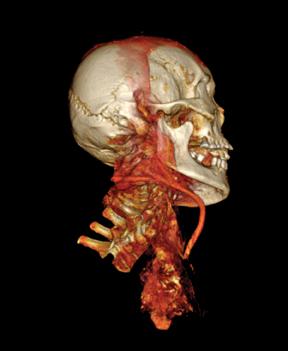

While the Horus study has previously reported atherosclerotic vascular calcifications on CT scans in ancient Egyptians, the Horus team’s new study compared patterns and demographic characteristics of this disease among Egyptians from both ancient and modern eras.[1] The authors compared the presence and extent of vascular calcifications from whole-body CT scans performed on 178 modern Egyptians from Cairo undergoing positron emission tomography (PET)/CT for cancer staging to CT scans of 76 Egyptian mummies (3100 BC to 364 AD). Patients undergoing cancer staging were selected for the study because these scans had already been completed for this group of patients as part of their cancer care.

The mean age of the modern Egyptian group was 52 years (range 14 to 84) vs. estimated age at death of ancient Egyptian mummies at 36 years (range 4 to 60). Vascular calcification (evidence of atherosclerosis) was detected in 108 of 178 (61 percent) modern patients vs. 26 of 76 (38 percent) mummies, with vascular calcifications on CT strongly correlated to age in both groups. In addition, the severity of disease by number of involved arterial beds also correlated to age, and there was a very similar pattern between the two groups.

“The CT scans show a surprising similarity in the amount and distribution of atherosclerotic calcifications between ancient Egyptians and men and women living in the U.S. today,” said James Sutherland, M.D., co-author and radiologist at Saddleback and Orange Coast Memorial in California. “This should lead to re-evaluation of the root causes of atherosclerosis and could lead to entirely new avenues of prevention and early treatment.”